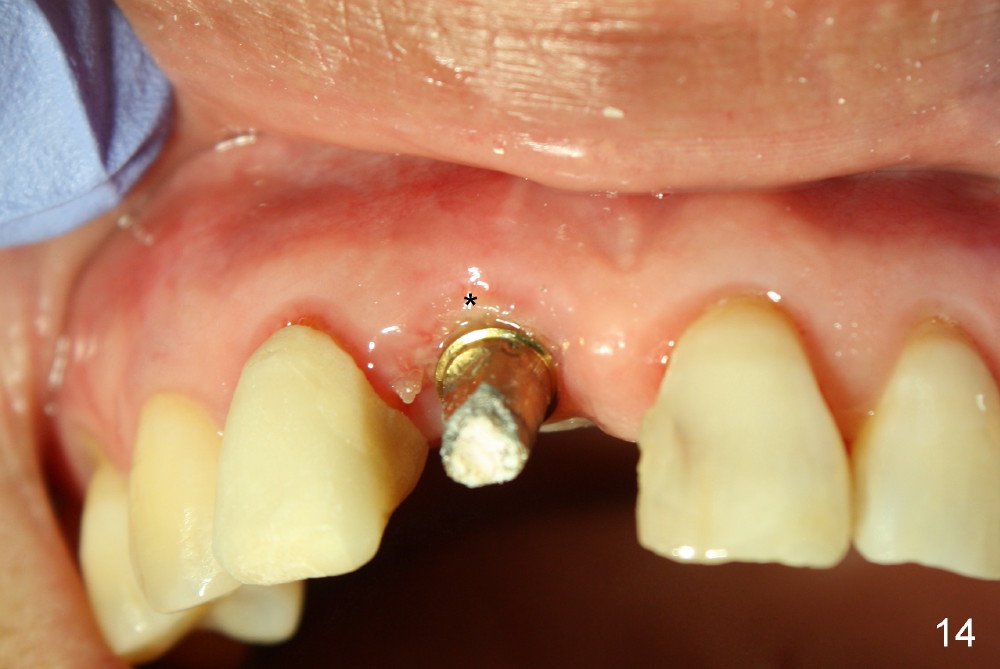

The patient returns for follow up 8 days postop and the labial margin of the provisional looks long. The metal crown is changed to a provisional at the visit. Eight days later, the provisional at the site of #8 is removed for labial margin trimming; the labial gingiva heals (Fig.14 *). The labial plate remains slightly convex (Fig.15). The labial margin of the provisional at the site of #8 is at the same level of that of #9.